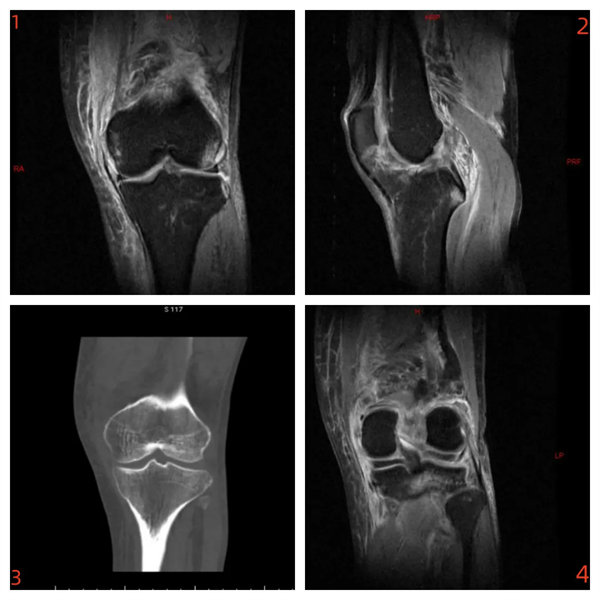

術前影像:

內側副韌帶斷裂(圖1)、前交叉韌帶斷裂(圖2)、脛骨平臺外側緣骨折(圖3)、內、外側半月板II-III°損傷(圖4)